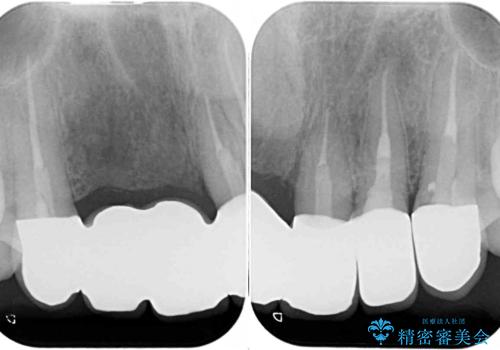

- 前歯を2本抜歯した後に装着した仮歯が長く見えるのが気になるとのことで来院された患者様です。

抜歯後には歯を支えていた骨が失われるため、歯肉が痩せてしまい、結果としてブリッジのダミーの歯を長くする必要があります。

歯肉が痩せてしまっている状態を改善するため、口蓋から歯肉の結合組織を採取し、移植することで厚みを増大させることとし、その後オールセラミックブリッジにて補綴治療を行うこととしました。

1回の歯肉移植により歯肉の厚みは大幅に改善されましたが、折角なのでもう少し大きくしたいとの要望があり、2回目の処置も行うこととしました。

厚みも高さも十分な歯肉量を獲得することができました。